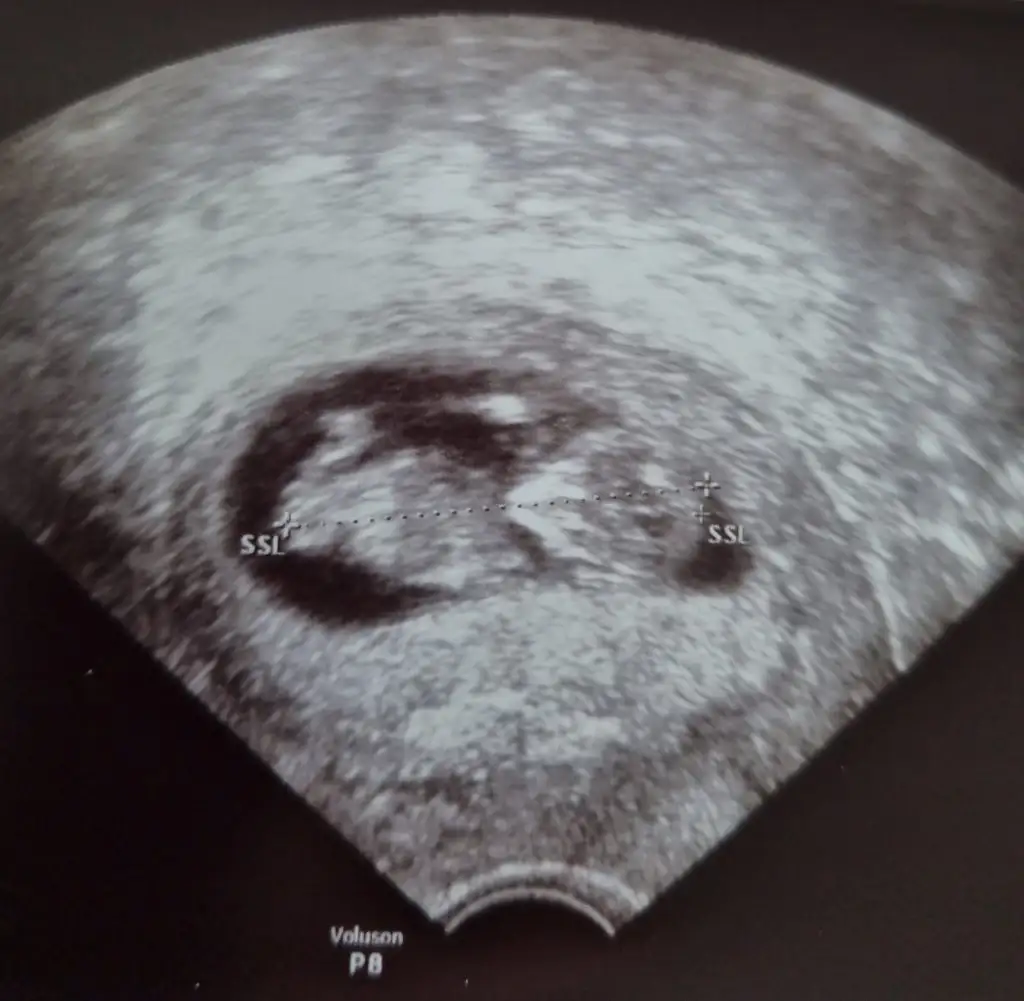

Skull teorisi ne göre yaparsin diye atmistimBaşı var bebeğin nubu görünmüyor

Nub gördümmu paylastinmi 11 12 13 haftalar kafaya göre kızSkull teorisi ne göre yaparsin diye atmistim

Coguda kafaya görr erkek diyo bende kiz hissediyorum nub bu var sirf bak bakalmNub gördümmu paylastinmi 11 12 13 haftalar kafaya göre kız

Buna göre ne diyosunCoguda kafaya görr erkek diyo bende kiz hissediyorum nub bu var sirf bak bakalm

Kız canim kafa için bak resim attimCoguda kafaya görr erkek diyo bende kiz hissediyorum nub bu var sirf bak bakalm

Ama benimkinin kafasi köseli degilmi yusyuvarlak degil sankiKız canim kafa için bak resim attimEki Görüntüle 2804795